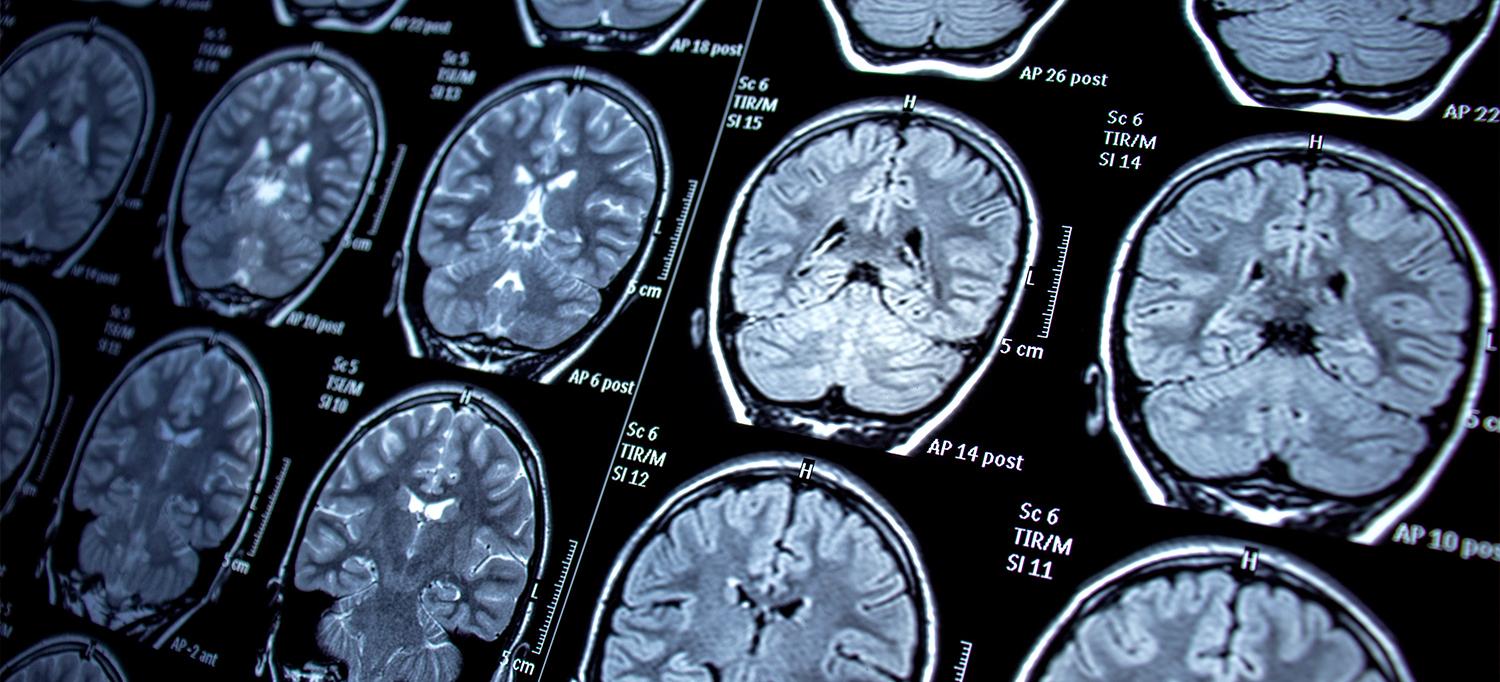

An analysis of adult human brain tissue reveals over 900 proteins tied to epilepsy. The brain disorder, estimated to affect more than 3 million Americans, is mostly known for symptoms of hallucinations, dreamlike states, and uncontrolled, often disabling bodily seizures.

Study results showed that altered levels of brain proteins predominated in the hippocampus, a structure located deep inside the skull and responsible for memory and learning. However, some 134 proteins were significantly changed in both the hippocampus and frontal cortex, the front third of the brain, which is also responsible for controlling thought and body movements. Most of the changed proteins were tied to genes in charge of protein production and linked to epilepsy in much smaller, earlier studies, but 4 of the 20 most-altered proteins had never previously been associated with the disorder.

Published in the journal Brain Communications online March 9, the new investigation focused on regions of the frontal cortex and hippocampus that previous imaging and neurological studies had identified as most impacted by seizures.